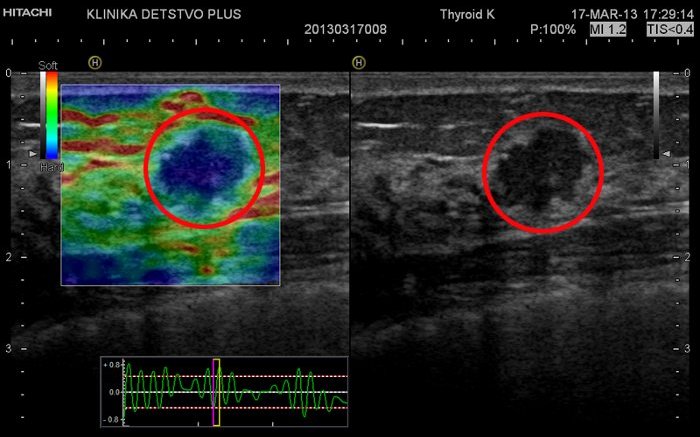

Впрочем, самое главное для пациентов, конечно, заключается в том, что вместе с аппаратом Hitachi Hi Vision Preirus в зеленоградскую медицину пришла соноэластография — новейший метод выявления опухолей на самых ранних этапах развития. — Любая ткань организма обладает определенными свойствами, в том числе — плотностью, эластичностью. Различные заболевания эти свойства ткани меняют, — объясняет Елена Алексеевна. — Так, воспалительные процессы и опухоли приводят к размягчению или уплотнению ткани, вследствие чего меняется ее эластичность. Соноэластография позволяет сравнивать эхосигнал, получаемый от патологического участка и здоровых тканей при нагрузке — мягком давлении обычным ультразвуковым датчиком, и судить о доброкачественности или злокачественности процесса. Эта технология применяется при исследовании молочных желез, щитовидной железы, лимфоузлов, мышц, других поверхностно расположенных органов и образований, органов малого таза у мужчин и женщин, некоторых внутренних органов.

Соноэластография дает врачу возможность четче визуализировать подозрительные образования в тканях, которые плохо различаются при исследованиях на обычных УЗ-аппаратах, и более точно определить истинные размеры опухоли. Этот метод позволяет дифференцировать кисту или воспалительный процесс, но, наверное, самое важное достижение соноэластографии заключается в возможности провести границу между доброкачественными и злокачественными опухолями.

— Или вот, противоположный результат, — Елена Алексеевна демонстрирует другую сонограмму. — Здесь вызвавшая подозрение область при соноэластографии, к сожалению, окрасилась в синие оттенки цвета, что с большой долей вероятности свидетельствует о злокачественной природе этой опухоли. Мы подозреваем рак, и в этом случае дополнительное исследование — биопсия — необходимо. Только оно поможет определить конкретный вид опухоли и назначить правильное лечение. У данного пациента злокачественный характер поражения был подтвержден. При этом чрезвычайно важно, что благодаря высокой разрешающей способности нашего аппарата мы можем выявить опухоль на самой ранней стадии, а значит гораздо раньше приступить к лечению и добиться полного выздоровления.

Изображение тканей в режиме соноэластографии на приборе Hi Vision Preirus (Hitachi): злокачественный характер очаговых изменений (рак)

Изображение тканей в режиме соноэластографии на приборе Hi Vision Preirus (Hitachi): злокачественный характер очаговых изменений (рак)